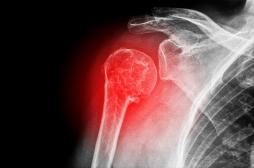

Densitométrie osseuse